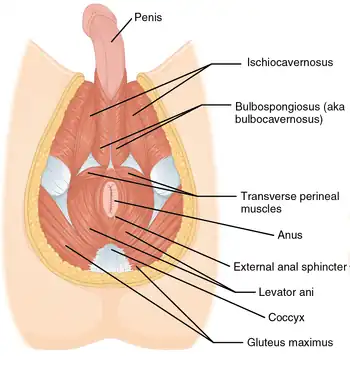

Muscles of the male perineum

Muscles of the male perineum Muscles of the female perineum